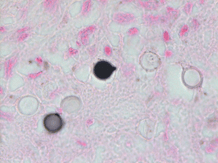

Premortem and postmortem cultures were not collected. Fontana-Masson stain of a section from the hilar lung tissue reveals yeast of varying size with a lighter shade in the center and a thick capsule, though the capsule does not stain and can instead be appreciated as a “halo” (Image 1). Fontana Masson stain also reveals narrow based budding (Image 2). Both findings indicate Cryptococcus neoformans.

The Fontana-Masson silver (FMS) stain is a histochemical technique that oxidizes melanin and melanin-like pigments as it reduces silver. FMS can be used to highlight the melanin-like pigment in Cryptococcus spp., including capsule-deficient variants because this pigment is cell-wall (and not capsule) associated. FMS is a very sensitive, but not completely specific stain, for Cryptococcus spp. as other yeasts and fungi can also produce melanin and melanin-like pigments.3 Though two C. neoformans yeast close together can resemble broad-based budding, Image 2 demonstrates the narrow-based budding.